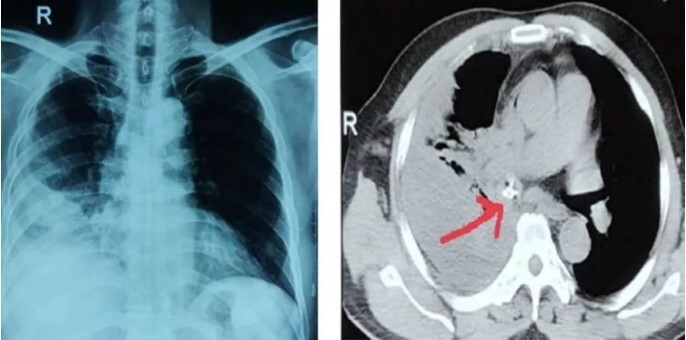

Nam bệnh nhân được người nhà chuyển đến Bệnh viện Đa khoa tỉnh Phú Thọ trong tình trạng đau tức ngực và khó thở.

Ngay sau khi nhập viện, bệnh nhân được chỉ định nội soi thực quản – dạ dày ống mềm lấy dị vật nhưng không thành công.